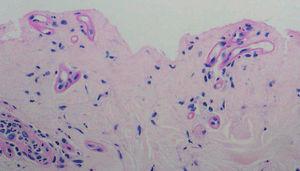

Fig. 3.--Depósitos perivasculares con la tinción del PAS.

El estudio histopatológico mostró una ampolla subepidérmica con ausencia de infiltrado inflamatorio. La técnica de PAS reveló la presencia de anillos hialinos perivasculares.

El estudio histopatológico recuerda a una PCT con una ampolla subepidérmica y con un escaso infiltrado inflamatorio. Los vasos de la dermis muestran depósitos de un material PAS positivo. Con microscopia electrónica se observa una reduplicación de la membrana basal y un depósito perivascular de un material fibrilar fino 5.